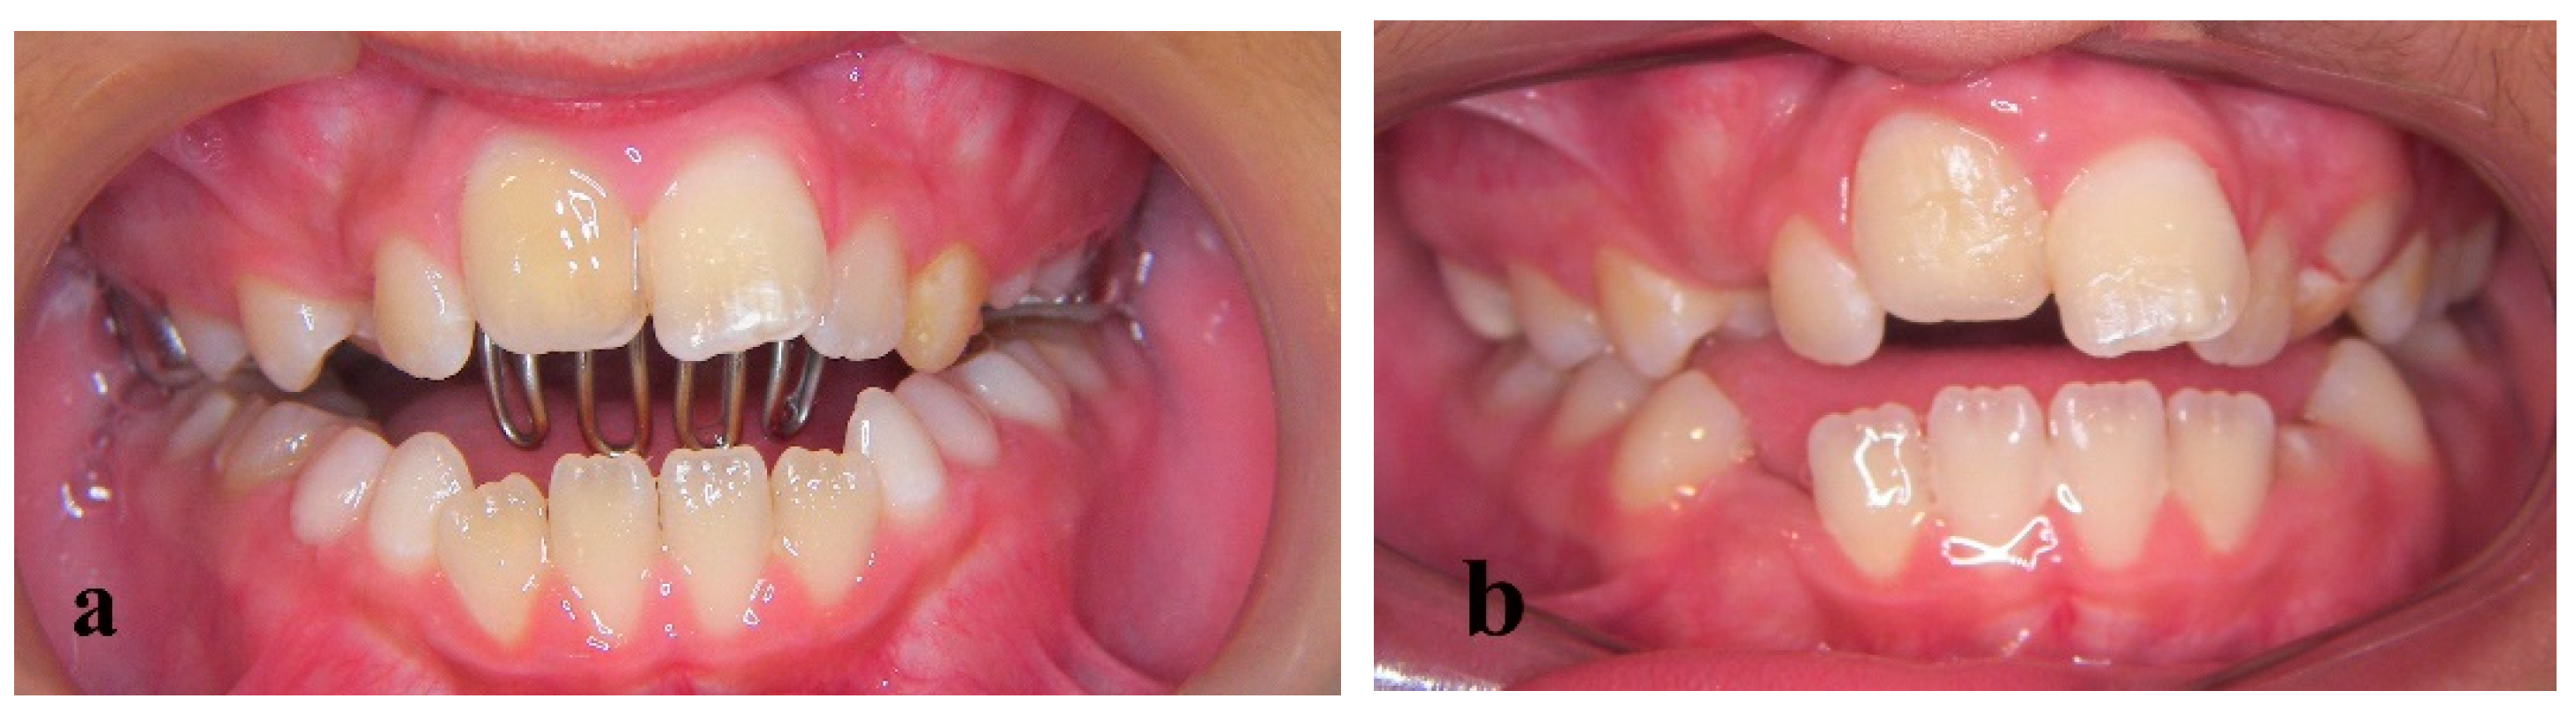

Treatment of an Avulsed and Ankylosed Incisor through Single Tooth Alveolar Osteotomy and Conventional Orthodontic Mechanisms

2. Materials and Methods

3. Results